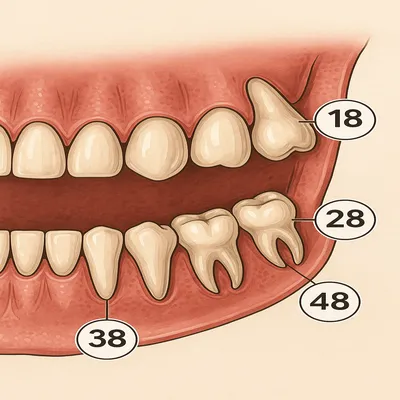

شمارهگذاری مولر سوم در فک بالا و پایین با نمای واقعی

در سیستم جهانی FDI دهان به چهار ربع تقسیم میشود؛ فک بالا سمت راست (۱۰۰)، فک بالا سمت چپ (۲۰۰)، فک پایین سمت چپ (۳۰۰) و فک پایین سمت راست (۴۰۰). در هر ربع، شمارهگذاری دندانها از وسط دهان شروع میشود و تا انتها ادامه دارد. بر این اساس:

دندان عقل بالا راست شماره ۱۸ است.

دندان عقل بالا چپ شماره ۲۸ است.

دندان عقل پایین چپ شماره ۳۸ است.

دندان عقل پایین راست شماره ۴۸ است.

بنابراین وقتی میپرسیم دندان عقل شماره چند است، در سیستم FDI پاسخ روشن و دقیق این است که دندانهای عقل با اعداد ۱۸، ۲۸، ۳۸ و ۴۸ مشخص میشوند.